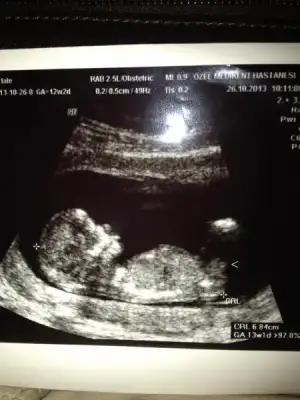

dr soylemeden siz gorun genital nub teorisi ( bebegin cinsiyeti)

Kimler kimler yazdı?herkesin 29 ekim bayramını kutlarım. benim fotoma da bakıp bir yorum yapabilir misiniz? 12 +2 de. sağdaki çıkıntı paralel gibi duruyor sanki. sizce o nub mu?

arkadaşlar sadece görebildiklerime yorum yapabiliyorum ama ben de tam bilmiyorum yani sadece tahmin ediyorum

bu bebiş erkek gibi eğer gördüğüm nubsa

Eki Görüntüle 843501 Eki Görüntüle 843502 Sanırım ben yüklerken biraz küçük yüklemişim şimdi en net 2 fotoyu seçerek tekrar yükledim. belirttiğim gibi bu resımde 11+4teyiz çok merak içindeyim lütfen yorum :)

nubu pararlel görünüyor erkeklerin dik oluyor eğer gördüğüm nubsa tabi canım

ama en iyi 13. haftada belli oluyor nuba göre

senin aslında doktor bilmesi gerekir bu haftanda

anladım doktor tam bişey soylemek istemedi artık ben çok kız istiyorum diyemi bilmiyorum ama bana erkek gibi geldi dedi sonraki aya çağırdı normal kontrole ama ben bu hafta başka bi doktora gidicem 16 haftalık dolu dolu inşallah kesin öğrenirim bu arada eğer o görünen nubsada çok uzun bi nub hayrlısı artık :)))

Eki Görüntüle 842353 resim buydu

bana erkek gibi geldi çok anladığımdan değil sadece gördüğüm nubsa eğer paralel değil baya dik hayrlısı olsun inşallah bu arada bende tam olarak öğrenemedim senin gibi araştırmadayım :)

bak doktor da erkek gibi demiş :) ama nubun da yanılma payı oluyor gönlünden ne geçiyorsa o olsun inşallahanladım doktor tam bişey soylemek istemedi artık ben çok kız istiyorum diyemi bilmiyorum ama bana erkek gibi geldi dedi sonraki aya çağırdı normal kontrole ama ben bu hafta başka bi doktora gidicem 16 haftalık dolu dolu inşallah kesin öğrenirim bu arada eğer o görünen nubsada çok uzun bi nub hayrlısı artık :)))

Teşekkür ederim cevapladıgin için. Ben anlayamadım da bacak engel olmuş nub görünümüne sanırım

Eki Görüntüle 843501

Eki Görüntüle 843502

Yokmu ßaşka yorumm Lütfenn :)

Merhabalar. Resimde işaret ettiğim şey nub mu sizce? Var mı tahmin yürütebilecek? Çok tşk

sanmiyorum onun altindaki olabilir erkek gibi

Eki Görüntüle 843501 Eki Görüntüle 843502 Yokmu ßaşka yorumm Lütfenn :)

görünmüyor görebildiklerime tahmin yapiyorum ben canim

Merhabalar. Resimde işaret ettiğim şey nub mu sizce? Var mı tahmin yürütebilecek? Çok tşk

o bacakları onun gerisindeki nub erkek gibi bebek

büyük ihtimal erkek gibi geldi bana

Canım sağol doğruymuş doktor erkek dedi :)) 14.haftada öğrendik ama anca yazabildim şimdi 18 hafta 3 günlük bebeğim